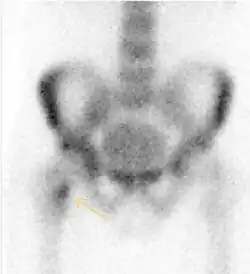

Nuclear Medicine

Bone scanning in people with hip pain can be complementary to other imaging studies, mainly in indeterminate bone lesions to clarify whether it is an active lesion with abnormal radiotracer accumulation. Nevertheless, MRI has replaced scintigraphy in the diagnosis of most of these conditions. An example is stress or insufficiency fractures: increased uptake is usually present in around 80% of fractures within 24 h, and 95% of fractures reveal activity by 72 h following trauma, showing an overall sensitivity of 93% and specificity of 95%. MRI is superior to bone scans in terms of sensitivity (99%-100%) and specificity (100%). Moreover, a bone scan does not provide detailed anatomical location of the fracture, and further imaging is usually required.[1]